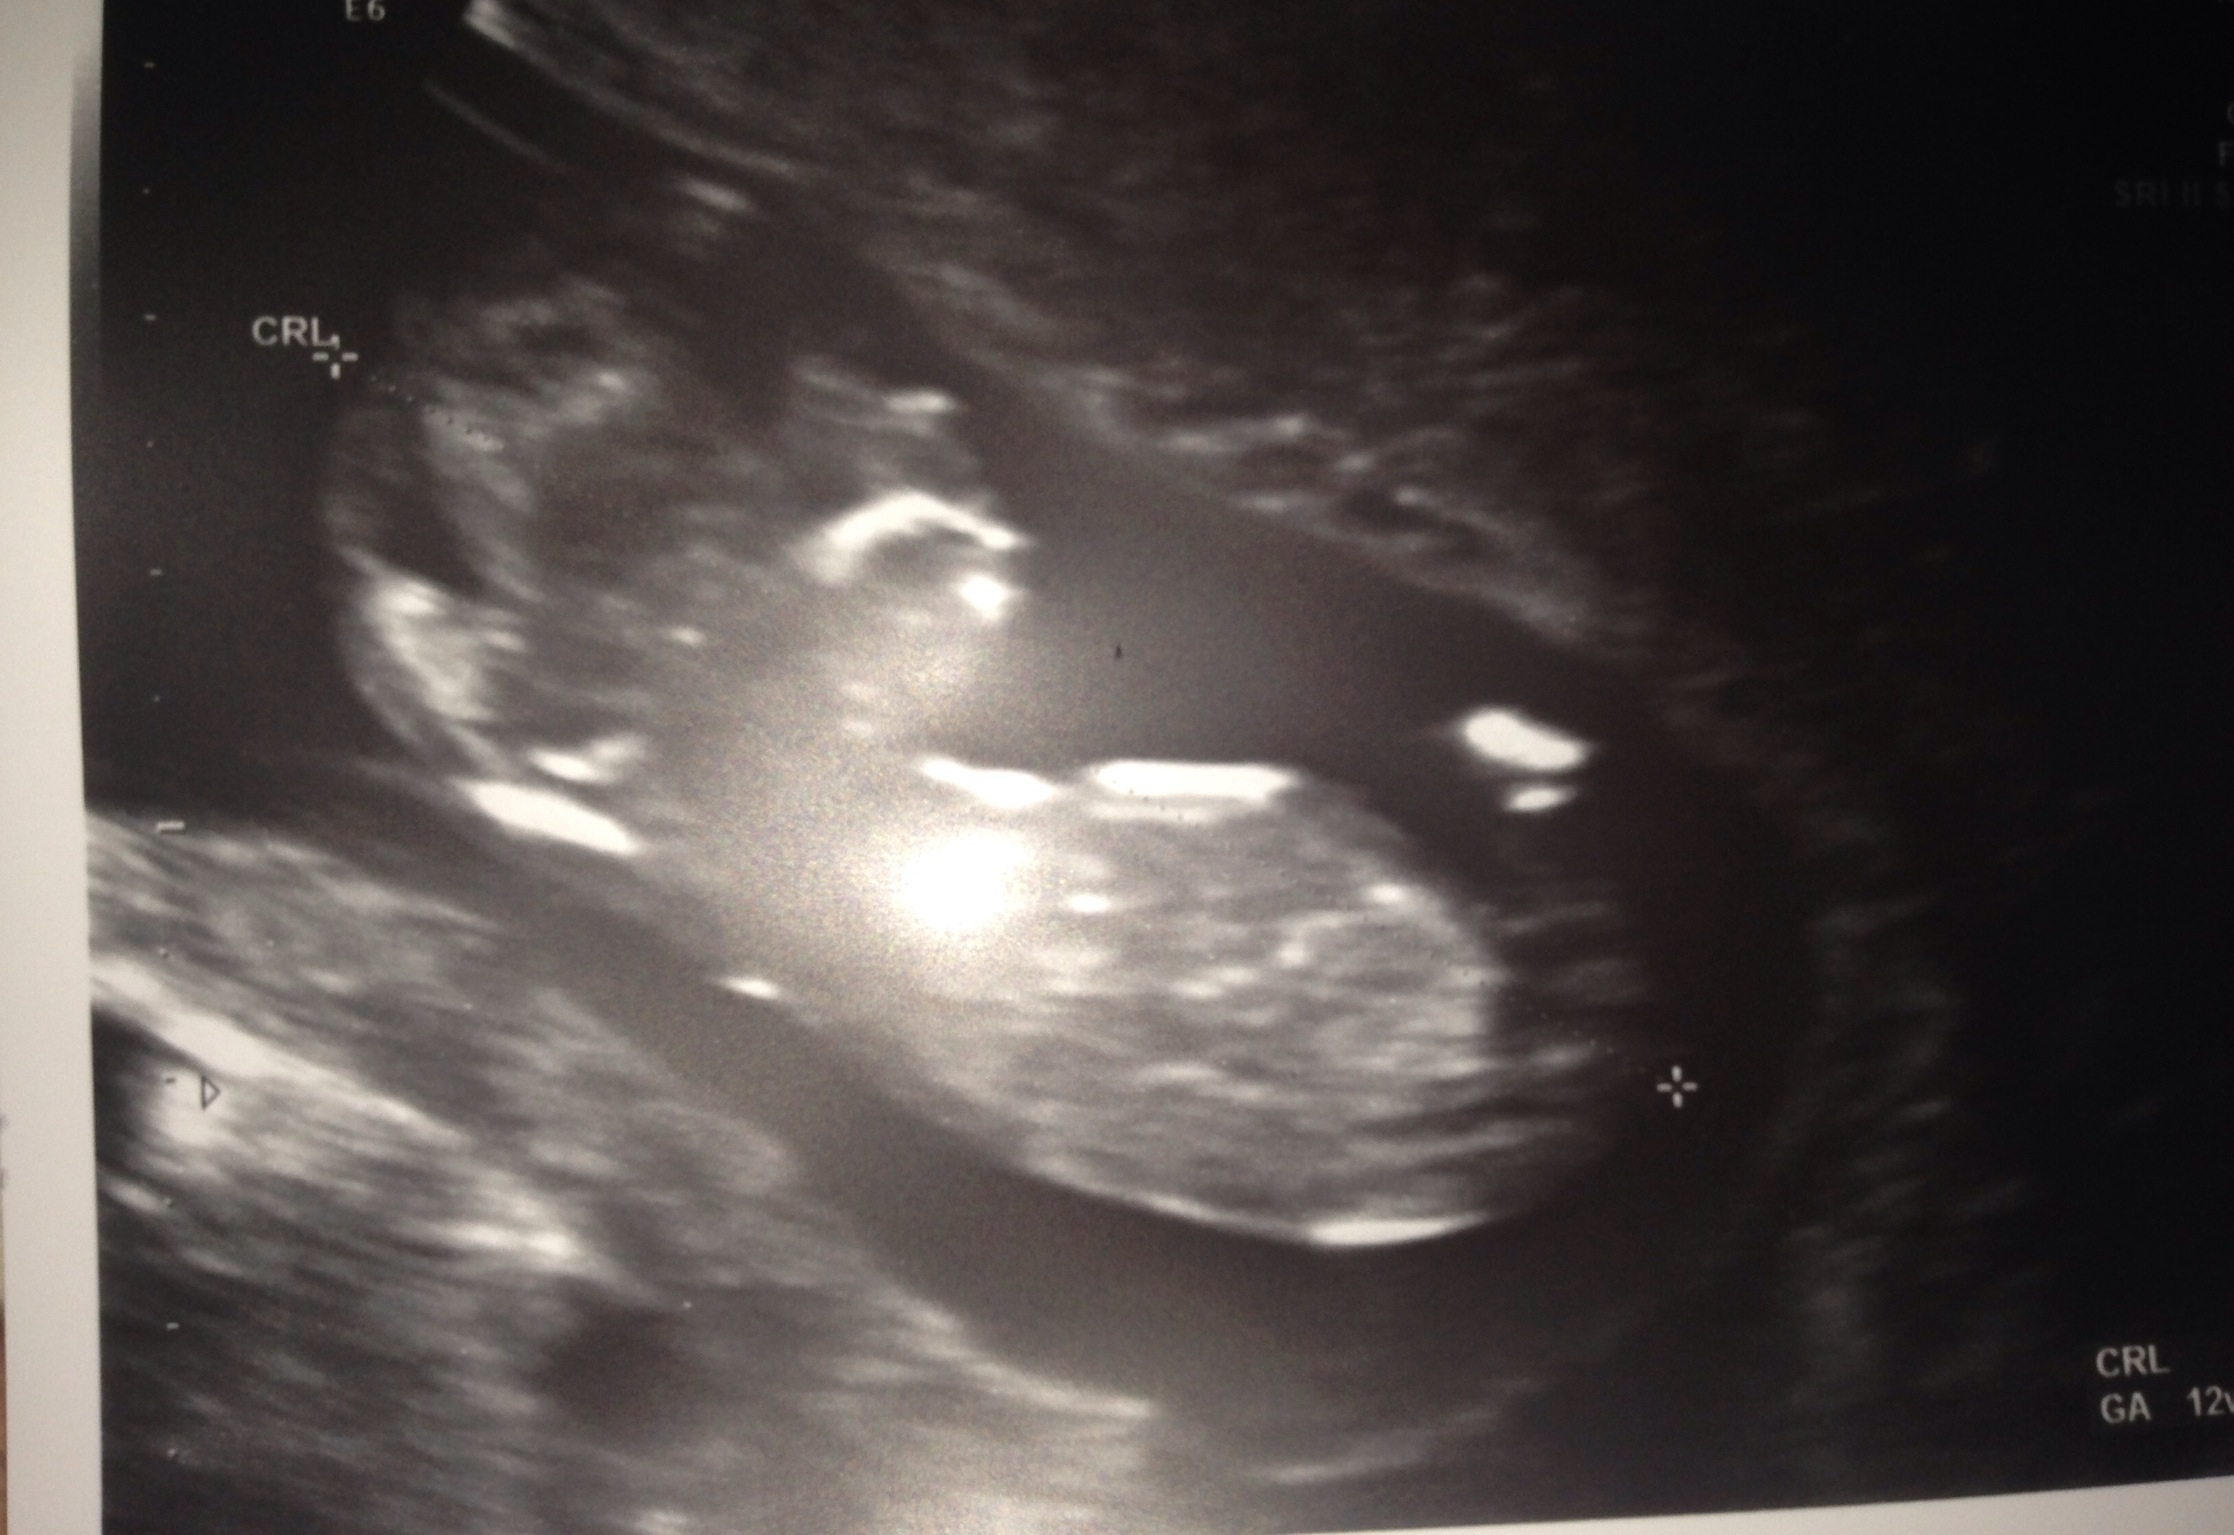

This was 13 weeks. Any guesses?Attachment 17730

Side note: baby was measuring 8 days ahead, so they changed my due date. That's why the photo says 11 weeks, 6 days as gestation. That's what I should have been.

I don't think this is a great nub pic...I don't see the spine very clearly and it seems baby is curled up a bit. Just for kicks though, I'll guess boy.

Unfortunately there is no clear nub and baby is not in the best position....but if I had to guess either way I would probably lean towards boy....but I certainly wouldn't but my money on it haha congrats on baby :) p.s. I think most of us can relate to nubsessing.....I'm guilty as charged ;)